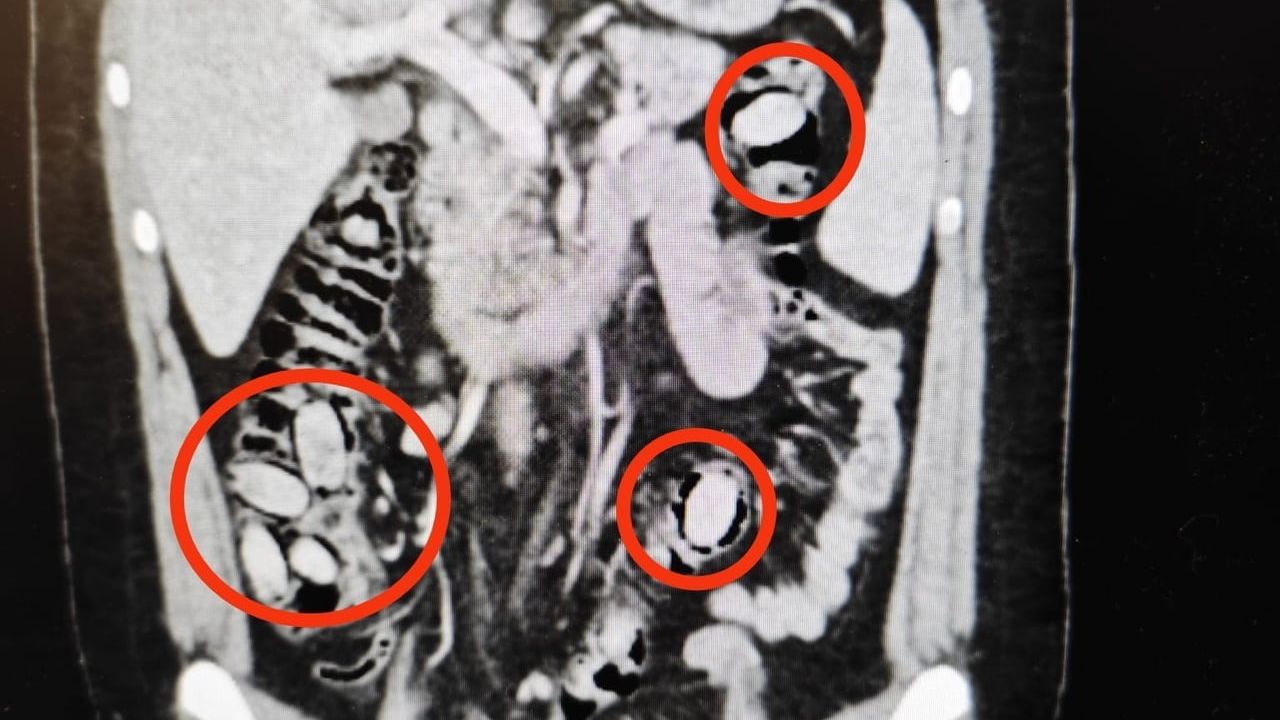

Yurtdışından Eskişehir'e gelen S.A. (25), kent girişindeki kontrol noktasında polis ekiplerinin dikkatini çekti. Şüphe üzerine hastanede yapılan detaylı tetkikler sonucunda şahsın yutmak suretiyle midesinde 44 kapsül metamfetamin taşıdığı tespit edildi.

Sağlık ekiplerinin cerrahi müdahalesiyle kapsüller şahsın bedeninden çıkarıldı. Tedavi sürecinin tamamlanmasının ardından S.A. çıkarıldığı mahkemece tutuklandı.

YURTDIŞINDAN ESKİŞEHİR’E 44 KAPSÜL UYUŞTURUCU MADDEYİ MİDESİNDE SOKMAYA ÇALIŞAN YABANCI UYRUKLU ŞAHIS POLİSİN DİKKATİ SAYESİNDE YAKAYI ELE VERDİ. AMELİYATLA MİDESİNDEN UYUŞTURUCU MADDELER ÇIKARILAN ŞAHIS ÇIKARILDIĞI MAHKEMECE TUTUKLANDI.